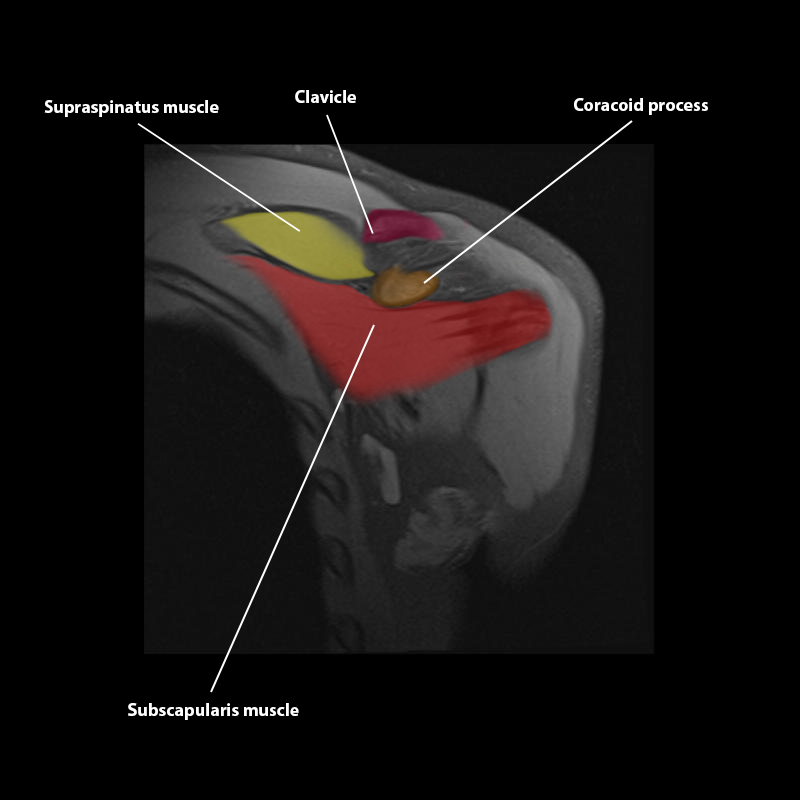

Shoulder MRI Anatomy